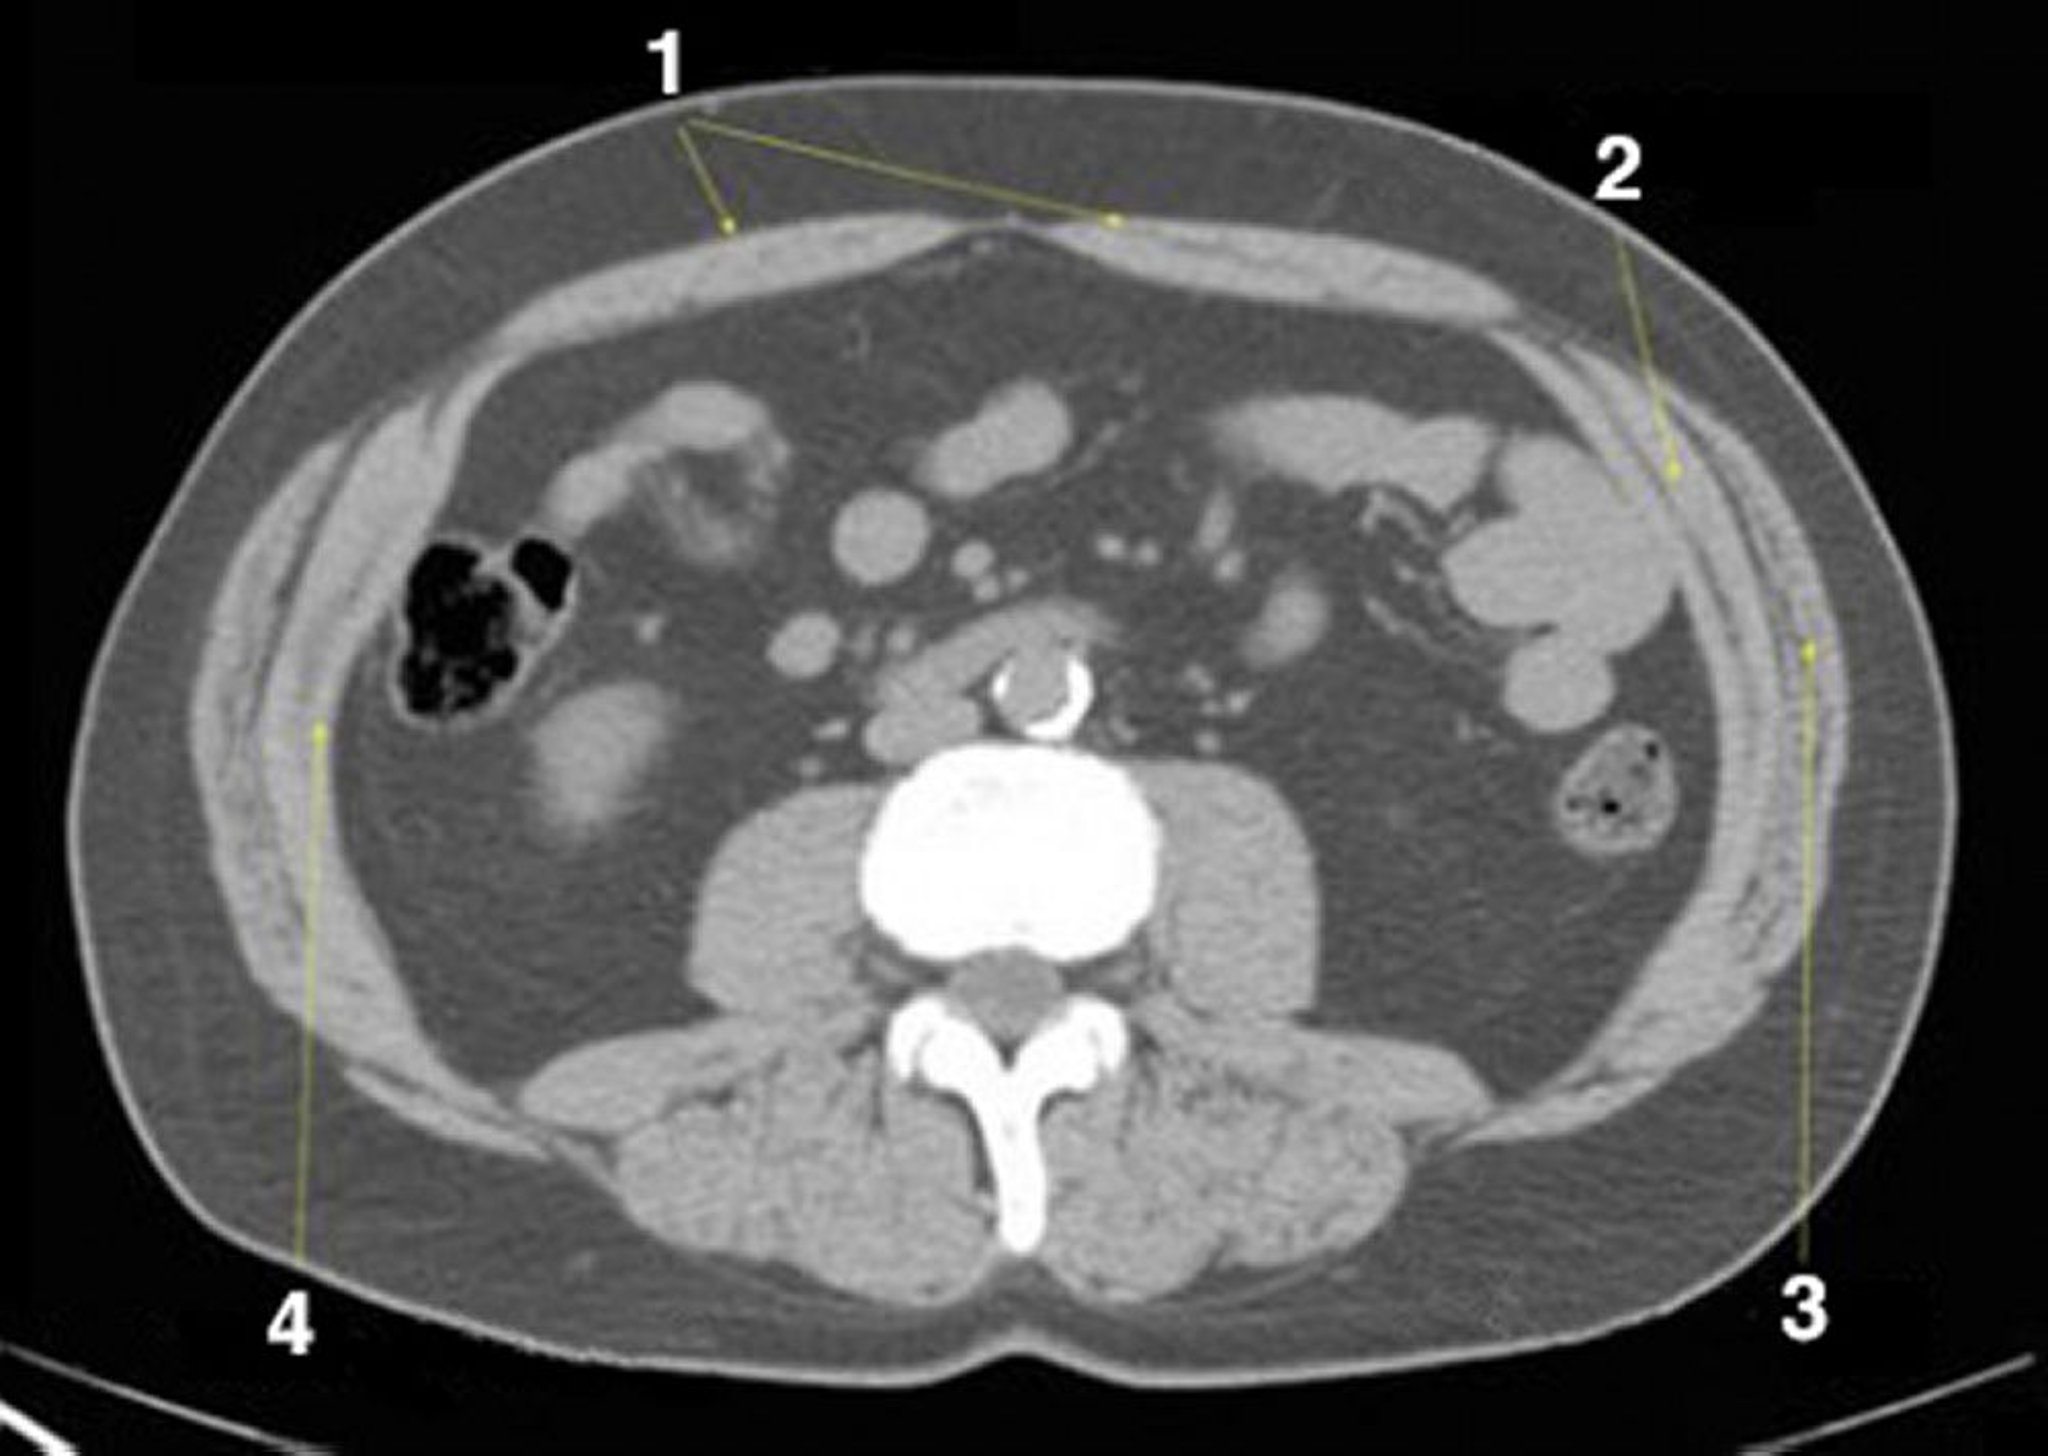

CT-Scan von Abdomen und Becken mit normaler Anatomie ohne Kontrastmittel (Folie 19)

1 = M. rectus abdominis; 2 = M. obliquus internus abdominis; 3 = M. obliquus externus abdominis; 4 = M. transversus abdominis.